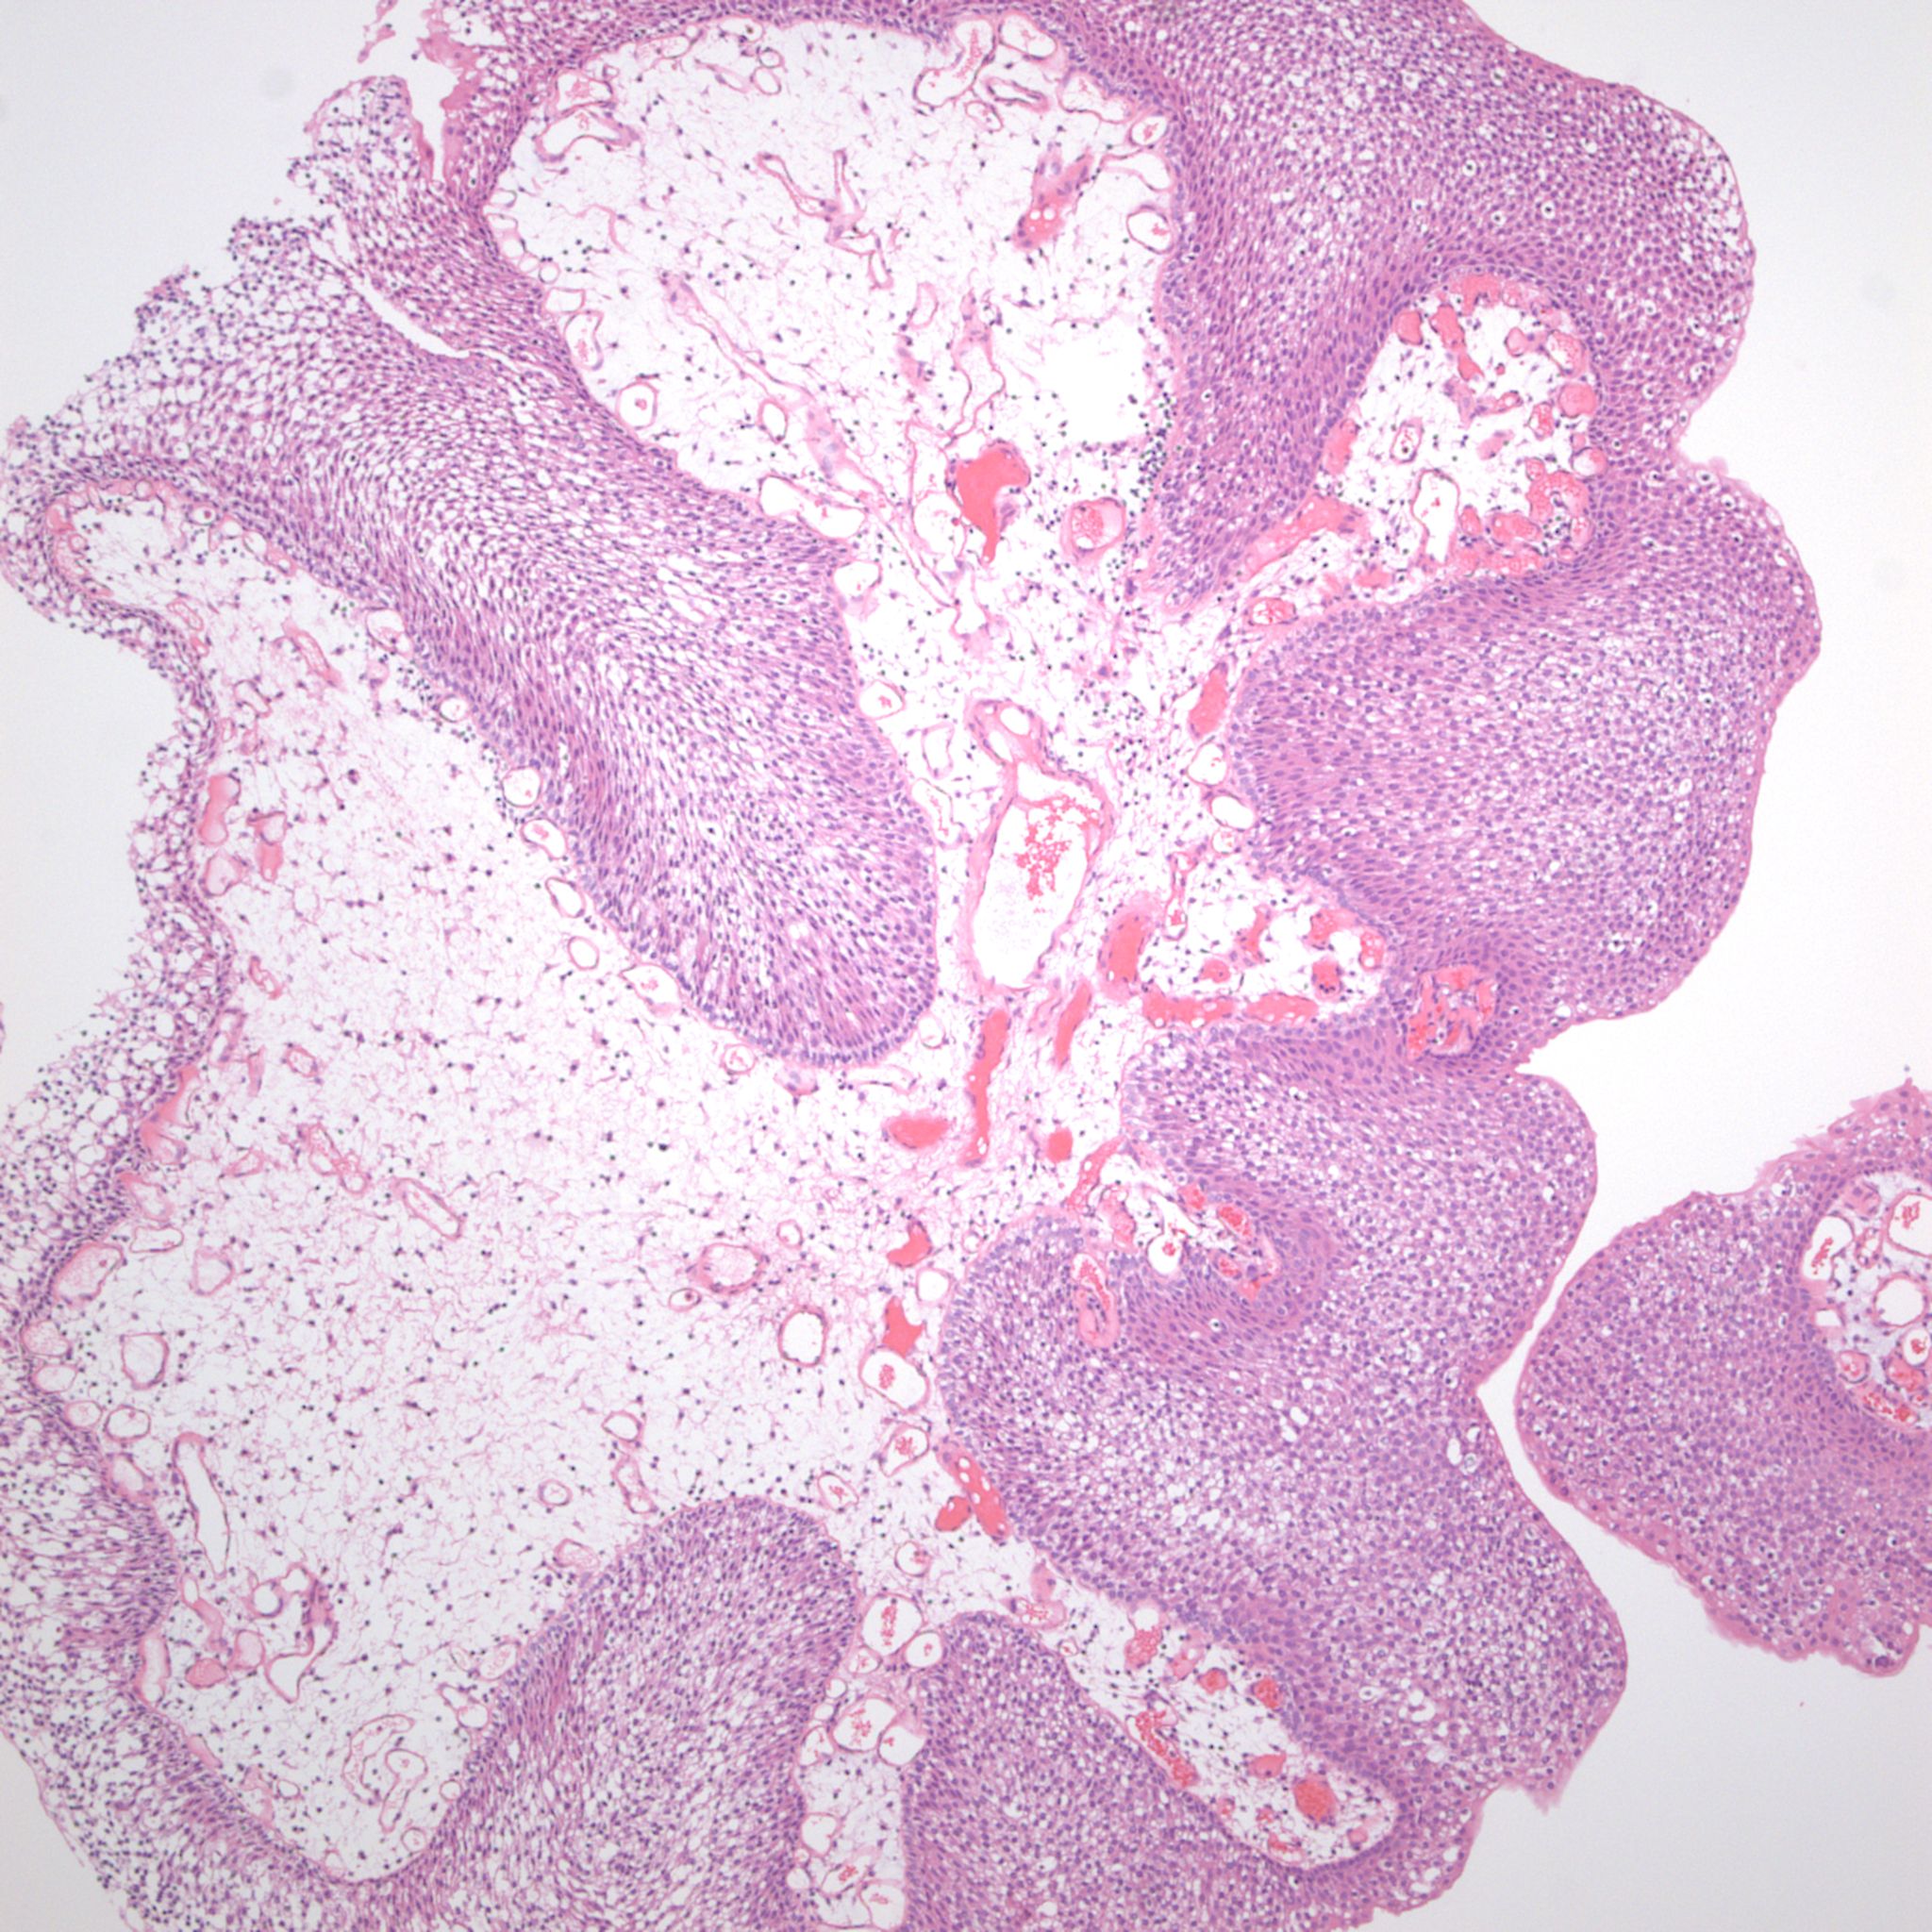

Bladder Papillary Lesions

Case ID: 315